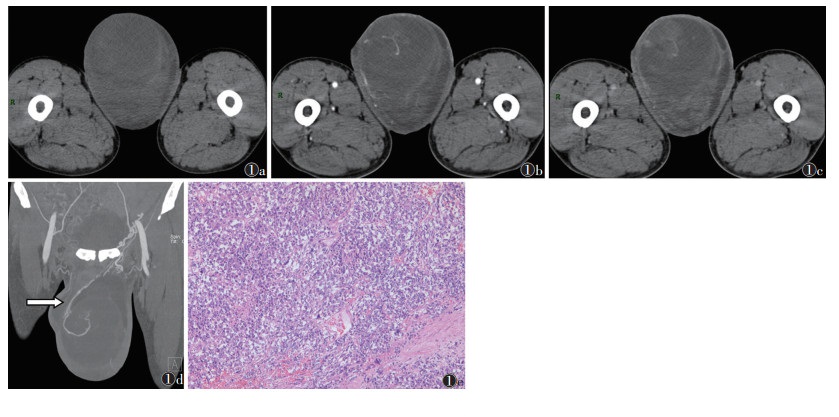

2 结果 2.1 精原细胞瘤22例中,20例来源于睾丸,12例右侧、8例左侧;腹内型隐睾精原细胞瘤1例;腹股沟隐睾精原细胞瘤1例。肿块位于睾丸者,病变侧睾丸不同程度增大(图 1);位于腹腔及腹股沟者,肿块体积较大,相应阴囊内睾丸未显示。肿块轮廓较清晰,强化更清晰,密度不均,可见低密度囊变坏死区,未见脂肪及钙化成分;肿块实质部分呈不同程度强化,可见分隔样强化,部分可见粗大的供血动脉(睾丸动脉)。4例伴鞘膜积液,1例伴腹股沟疝。

| 注:患者,男,49岁。图 1a~1c分别为平扫、动脉期和静脉期图像,左侧睾丸见混杂密度肿块,体积较大,内见多发液化坏死区;动脉期肿瘤实性成分轻中度强化,囊性坏死区无强化,分隔强化,未见脂肪及钙化成分;静脉期肿瘤内供血血管强化程度减退。图 1d为MIP图像,示肿块内见粗大供血动脉(睾丸动脉)(白箭)。图 1e为病理图像,示肿瘤细胞弥漫性增生伴散在淋巴细胞浸润,排列成片状、巢状或条索状,细胞异型性大,具有明显的细胞膜,核分裂象常见(HE染色,高倍放大) 图 1 睾丸精原细胞瘤CT图像及病理图像 |

精原细胞瘤属低度恶性肿瘤,好发于中青年,多为单侧,右侧略多于左侧,本研究与文献[2]报道一致。睾丸下降不全是该病发生的最重要诱因,隐睾患者发生睾丸肿瘤的概率明显高于正常人[2]。本研究中,20例肿瘤位于睾丸内,1例位于腹腔内,1例位于腹股沟区。CT平扫示:肿块密度大多较正常睾丸组织密度稍高、较均匀,边界清晰,睾丸白膜较韧厚,肿瘤极少突破白膜向外侵犯[3]。睾丸精原细胞瘤主要由睾丸动脉供血,血供较丰富,增强扫描病灶边缘和/或瘤内呈明显分隔样强化,实性部分呈轻中度强化,且强化程度较分隔样强化弱。分隔样强化是精原细胞瘤特征性表现,病理基础为肿瘤内的纤维血管分隔强化[3-4]。本研究中大部分为分隔样强化,与文献[4]报道一致。增强扫描动脉期于肿块边缘见增粗扭曲的睾丸动脉供血,静脉期见增粗扭曲的睾丸静脉引流,具有特征性[5-6],国外学者将其称为睾丸血管蒂征[7]。本组可见增粗的睾丸动脉供血和睾丸静脉引流,未见血管扭曲。